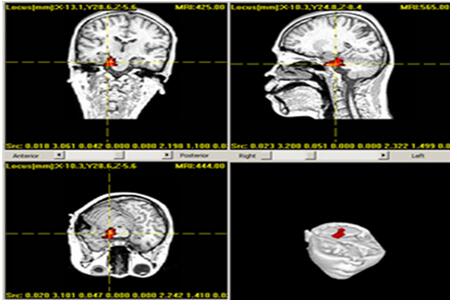

病例1,女,21岁,发作性四肢抽搐伴意识不清20余年。患者于7月龄起病,表现为先兆(害怕)、面色发红、嘴唇紫绀,左上肢过度运动,双眼左视,咂嘴,四处走动,持续约1~2 min,发作后言语不清。病初2~3 d发作1次,术前发作5~6次/月。服用药物治疗效果欠佳。术前MRI检查显示双侧海马硬化。VEEG显示发作间期:双侧颞区棘-慢波,发作期:双侧颞区慢活动。传统MEG(5~80 Hz)定位显示致痫灶位于双颞,高频MEG(80~250 Hz)分析示致痫灶位于右颞(图1)。结合定位结果,对患者行双侧额颞深部电极置入术,术后经长程脑电监测,明确异常放电区域位于右侧海马、杏仁核。遂行右侧海马、杏仁核电极毁损术。术后12个月随访,患者临床症状明显缓解,发作1次,Engel分级I级。

1A:5~250 Hz滤波范围脑磁图信号(红色双线范围内为棘波放电,蓝色箭头所示为高频信号);

1B:频谱分析显示红色箭头处信号功率谱最高(频率约为173 Hz);

1C:高频信号(173 Hz)脑磁图定位:右侧颞叶内侧

图1 应用高频信号脑磁图定位致痫灶(患者1)

Fig1 Localization of epileptogenic zones by high frequency signals